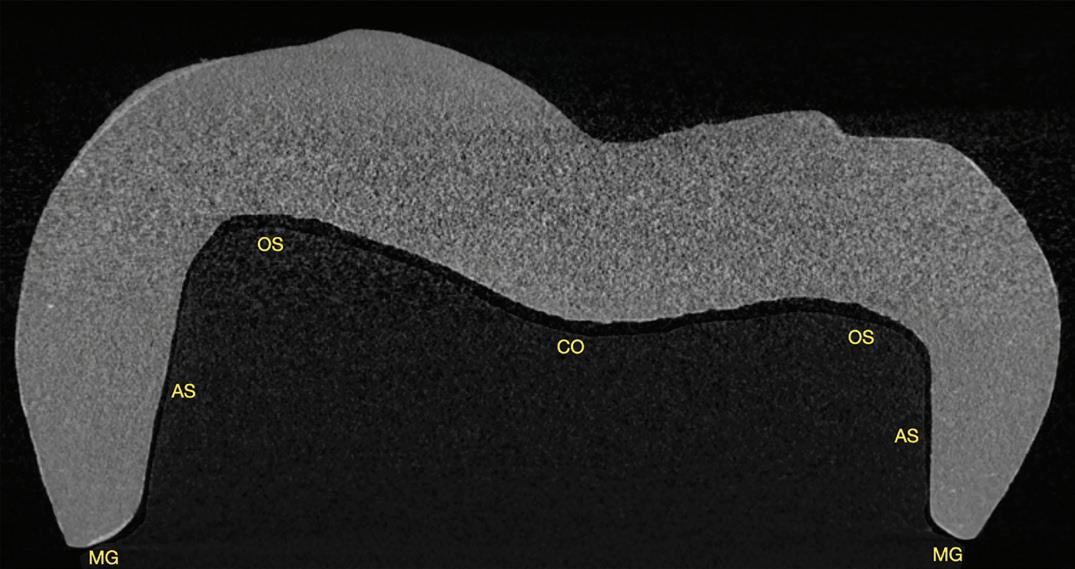

A periapical radiograph and a limitedfield-of-view cone beam computed tomogram of teeth 14 and 15 were taken, and no radiographic signs of apical periodontitis related to these teeth were noted that day (Fig 1). Sensibility tests were also performed. Tooth 15 responded normally to palpation and to bite and felt “different” on percussion (not painful, which is an important distinction to make). Tooth 14 responded

normally to palpation, percussion, and bite. Cold placed on tooth 14 triggered a significantly elevated, throbbing response that lingered more than 1 minute. Of all the tests performed, the cold on tooth 14 most closely replicated the pain of her chief complaint.

We reviewed treatment options, including no treatment. She elected to have endodontic therapy on tooth 14 performed that day. Local anesthetic was administered, and a dental dam was placed. This molar was slightly unusual in that I obtained patency in the palatal, distobuccal, and second mesiobuccal canals (MB2) that day, but the first mesiobuccal canal (MB1) was still not patent. Usually, it is MB2 that is the hardest to instrument. Calcium hydroxide medicament and a provisional restoration were placed. The patient was scheduled to return in 2 weeks for completion of endodontic therapy on tooth 14.

When she returned, I asked about her symptoms. The overall pain had reduced significantly, and the pain in tooth 15 with lateral pressure was gone, but there was still a deep ache in the area, now focused near tooth 15. She noticed a throbbing in the area with positional changes, such as sitting up and bending over. Sensibility tests were performed again. Tooth 14 responded normally to percussion, palpation, and bite. Tooth 15 responded normally to palpation, and percussion and bite elicited a moderately painful response (different from the results of the sensibility

Fig 2. Postoperative radiograph of teeth 14 and 15.

Fig 1. Preoperative radiographs. A. Tooth 14. B. Tooth 15.